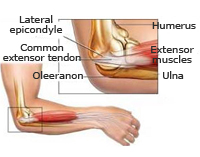

Fracturas de olécranon

El olécranon es la parte superior del cúbito que articula con el húmero para que podamos realizar la flexión y extensión de nuestro codo. Una fractura de olécranon supone la imposibilidad para la realización de esta función. Ocurren tanto en el paciente de edad avanzada como en el joven y suele ser por caídas con el codo en flexión. Dada su relevancia en el movimiento del brazo su reparación debe ser rápida y precisa para evitar secuelas en la bisagra del codo. A través de procedimientos mínimamente invasivos se puede conseguir la restitución articular minimizando los riesgos de grandes cirugías e iniciar el movimiento en un breve período de tiempo.